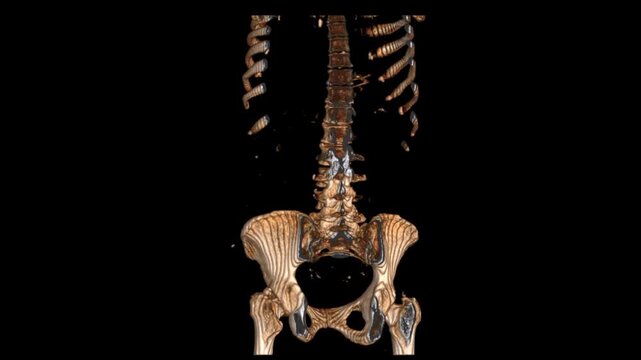

High-resolution STIR coronal VR movie of the lumbar spine, providing detailed visualization of vertebrae, intervertebral discs, and soft tissues. Ideal for radiologists, orthopedic specialists,

00:09